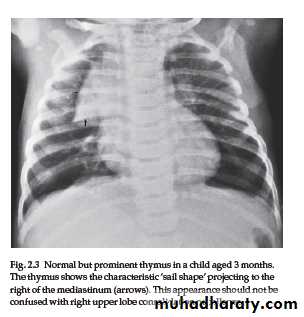

Normal thymus gland ( sail shape sign )